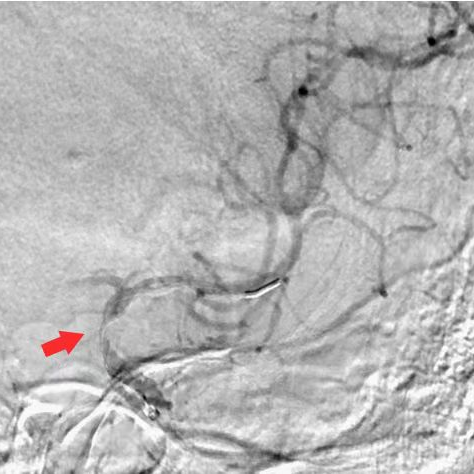

术前DSA

释放4×30mm取栓支架,可见支架局部打开不良,提示管腔重度狭窄。造影未见明显血栓征象,未行抽吸,拟直接行球囊扩张。